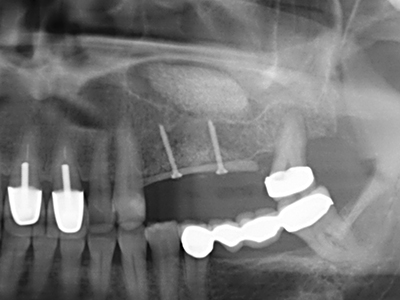

Sollen chirurgische Eingriffe mit unmittelbarer Knochenbeziehung an empfindlichen Strukturen wie Blutgefäßen oder Nerven erfolgen, so bergen rotierende Instrumente ein erhebliches Potential an iatrogener Schädigung. Gerade bei Nervdarstellungen nach iatrogener Schädigung, oder aber im Zuge einer Nervlateralisation für resektive und rekonstruktive Eingriffe oder Implantatinsertionen können piezoelektronische Geräte hilfreich sein Knochendeckel zu präparieren und nervnahe Hartgewebsanteile zu entfernen (Abb. 17-20). Ein leichter Kontakt des Nervstrangs zur Piezospitze bleibt dabei in der Regel folgenlos – allerdings kann eine unvorsichtige Vorgehensweise mit sägeartigen Bewegungen bzw. Ansätzen bei noch vorhandener knöcherner Unterlage durchaus temporäre oder aber auch permanente Nervschädigungen verursachen. Das Risiko einer solchen Schädigung wird jedoch als wesentliche geringer eingeschätzt als unter Anwendung von Säge- oder Fräsinstrumenten (Pereira, Gealh et al. 2014).